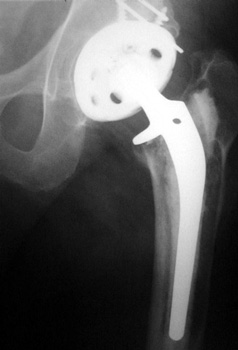

OSTEOLYSIS—Gruen zones 2 and 3, with markedly thinned femoral cortex, placing patient at risk for pathologic fracture

OSTEOLYSIS—ABOUT ACETABULAR COMPONENT GRUEN ZONE II, WITH PATHOLOGIC FRACTURE

OSTEOLYSIS

Multifocal and massive, involving Gruen zone III of acetabular cup and Grune zone 1,2, and 6 of femoral component

Radiograph and CT